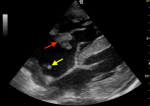

A 32-year-old man with end-stage kidney disease secondary to chronic glomerulonephritis, on maintenance haemodialysis via a right internal jugular central venous catheter for three months, presented with a one-day history of worsening dyspnoea, fever, chills, non-productive cough, and central chest pain. On examination, he was febrile with a temperature of 38.6°C, tachycardic at 126 beats per minute and blood pressure was 150/98 mmHg. His oxygen saturation was 88% on room air which improved to 96% with supplemental oxygen. Chest examination findings were consistent with bilateral pleural effusions. Jugular venous pressure was not elevated and no murmurs were heard. Point-of-care ultrasound demonstrated a large echogenic mass attached to the anterior leaflet of the tricuspid valve consistent with vegetation (red arrow), with the tip of the central venous catheter visualized within the right atrium (yellow arrow). Mild pericardial effusion and bilateral pleural effusions were also noted. Laboratory evaluation revealed marked leukocytosis with a white blood cell count of 28.6 x 109/L and neutrophil predominance, with severe anaemia (haemoglobin 7.2 g/dL). Blood cultures were obtained for suspected infective endocarditis following the ultrasound findings and empiric intravenous antibiotic therapy was initiated promptly. However, the patient deteriorated rapidly and died the following day. This image highlights the importance of maintaining a high index of suspicion for catheter-related infective endocarditis in patients undergoing haemodialysis. It demonstrates the critical role of point-of-care ultrasound in the early detection of life-threatening cardiac complications associated with central venous catheters.

Figure 1: point-of-care ultrasound image demonstrating a tricuspid valve vegetation (red arrow) and the tip of a central venous catheter in the right atrium (yellow arrow)